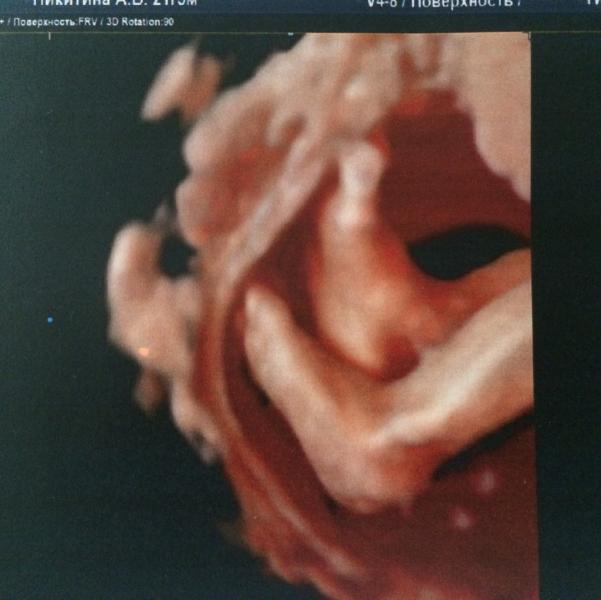

А у нас вот такие сладкие пятки 🙈😍 Сегодня были у Справцевой. Все посмотрела, рассказала как лежит, где спинка и все-все-все. Сделала много фоточек нашей принцессы, хотя это было не просто ( во сне малышка лицом поворачивается в позвоночнику и прижимает личико к стенке матки или закрывает ручкой) Алла показала нам длинные реснички нашей крошки и сказала что уже есть причёска)

Мы тоже на 26 неделе к ней ходили)И тоже фотку со сладкими пяточками имеем)))И мне тоже показалось,что сын на меня похож😂Справцева👍

Сладкие пяточки😍😍😍 Скажите, а полностью принцесса на монитор вошла? Мы тоже планируем на 25-26 неделе узи...

@denisovna16, нет, это просто 3д УЗИ. На память